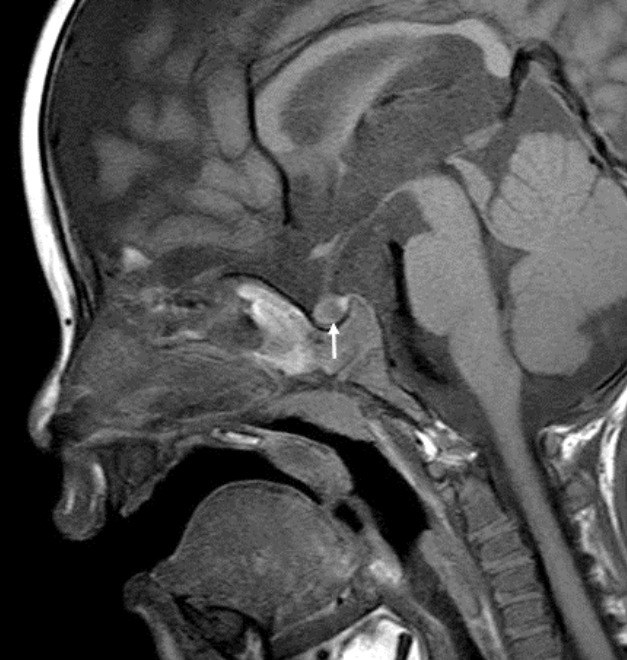

促甲状腺激素释放激素刺激试验显示TSH反应过度(基线TSH 7.02 μIU/ml; 30分钟88.55 μIU/ml; 60分钟73.4μIU/ml; 90分钟79.27μIU/ml; 120分钟64.41μIU/ml)。头颅磁共振造影未见垂体腺瘤证据;然而,发现了拉氏裂囊(图1)。甲状腺超声显示大小、轮廓、实质回声和血管性均正常,无结节。99m锝甲状腺扫描显示两侧甲状腺叶增大的摄取。

患者 12 个月大时的蝶鞍磁共振成像扫描。 除 Rathke 裂囊肿(箭头)外,矢状 T1 加权图像正常。